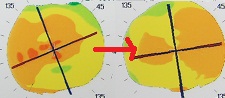

黄斑円孔の手術に関しては、?で記載しましたが、簡単におさらいすると、目の中に器械をいれて、内境界膜という網膜の表層の膜を剥離し、網膜を柔らかくします。その後、目の中に空気を入れてうつ伏せをすることで、円孔の周囲の網膜を浮力で引き寄せて、穴を閉じる。という方法です。

?手術の効果で、青や緑の網膜を中心部に引き寄せます。

?青の部分の網膜が、視野の中心部の視界を担うようになります。